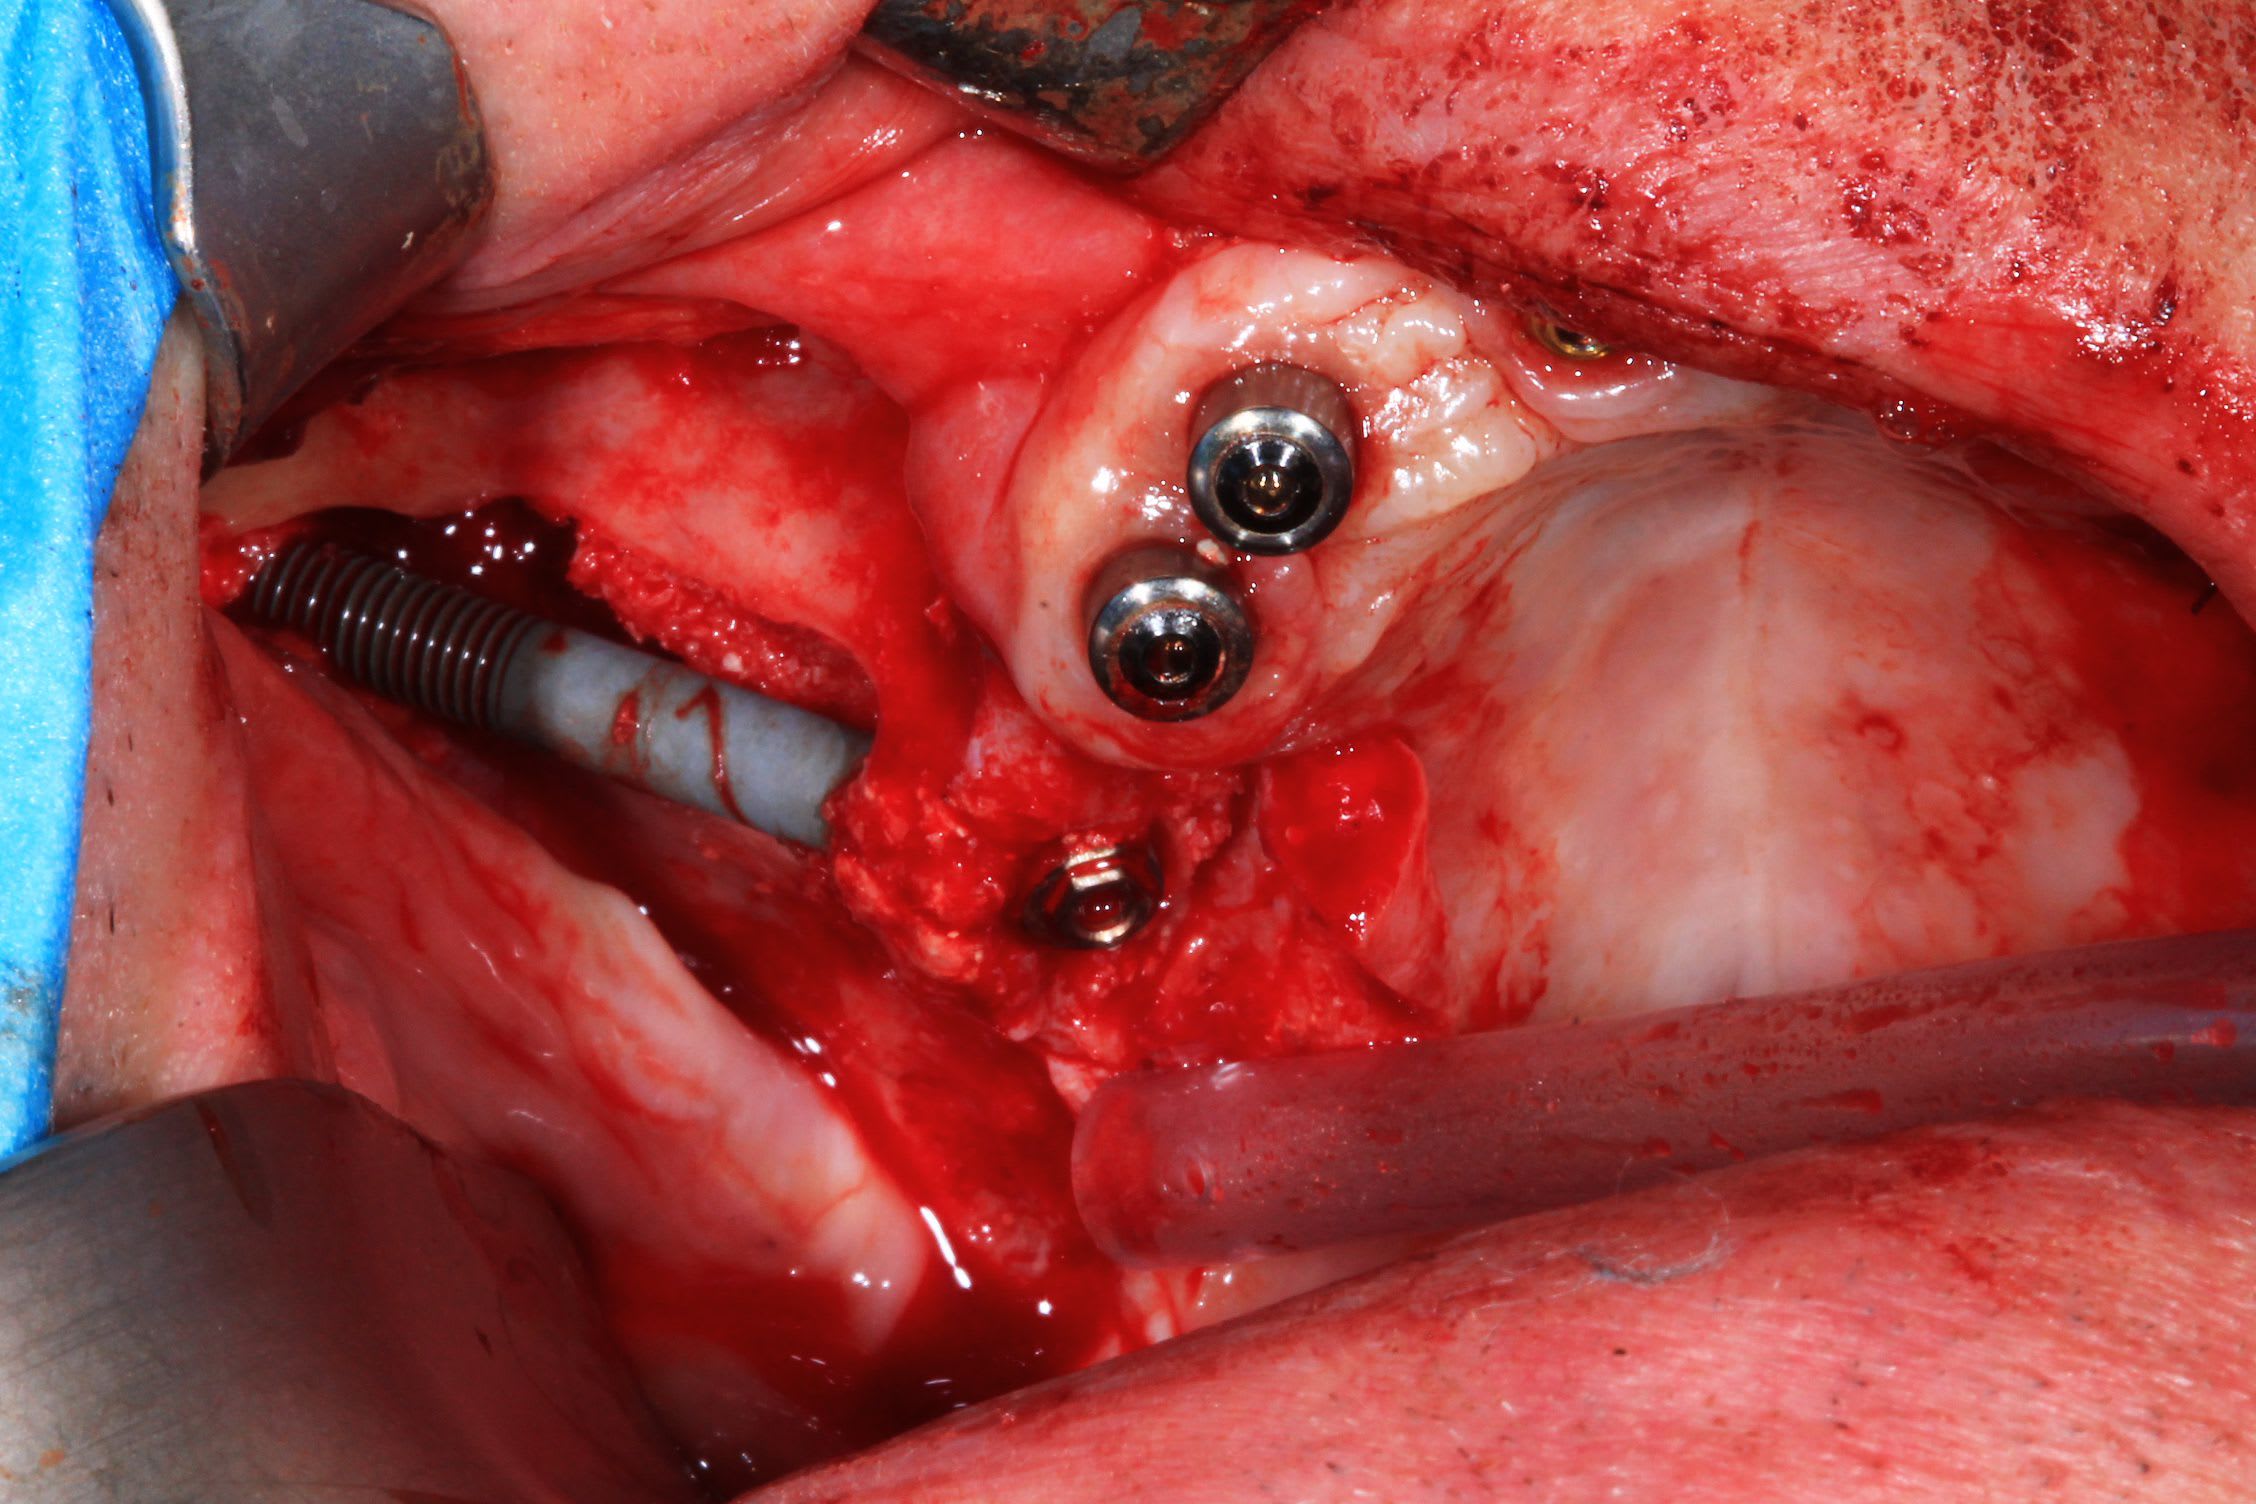

cas 3 : patient 50 ans. avoir des 7 est plus important . implants plus court : 4 de 12, un 14 et un 10. émergence des implant en 14 24 : obligation de chercher un appuis postérieur : deux ptérygoidiens.

Pas de guide à étage : guide appuis osseux, bridge a armature métal avec pilier collé en bouche avec indexation du bridge grâce aux clavettes du guide.